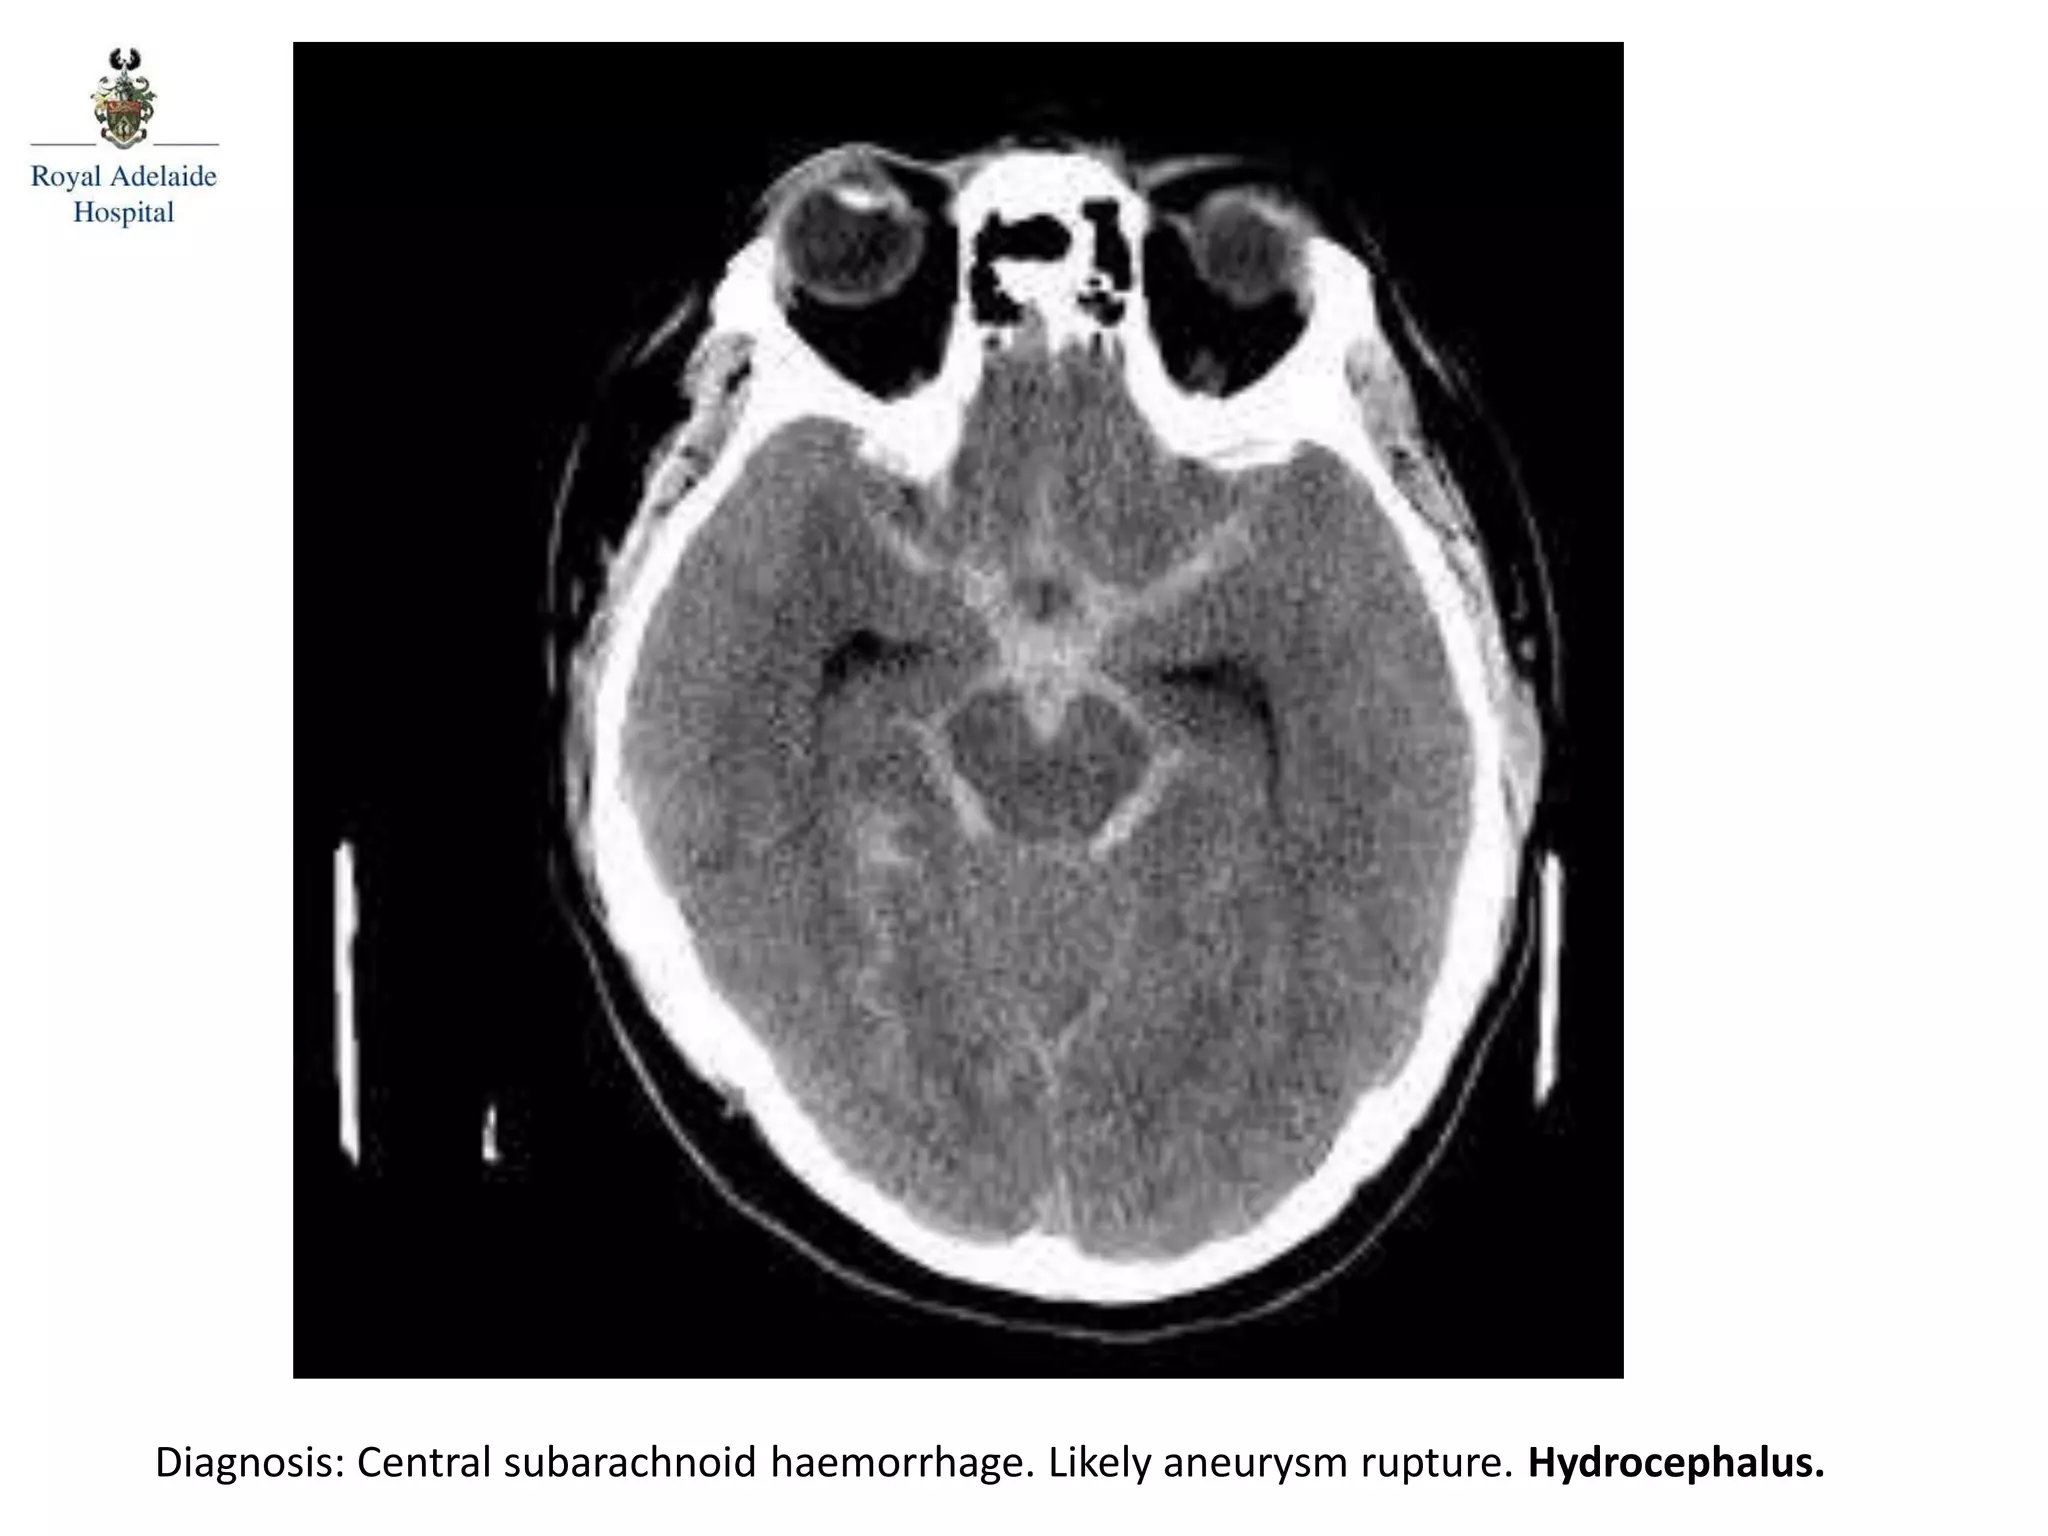

The document outlines multiple diagnoses from head CT cases, including small left basal ganglia bleed likely due to hypertension, various types of subdural and subarachnoid hemorrhages, and evidence of hydrocephalus. It details traumatic origins of some hemorrhages and notes obstructing masses and atrophic changes. Overall, there are significant findings indicating complications related to cerebral hemorrhages and ventricular enlargement.